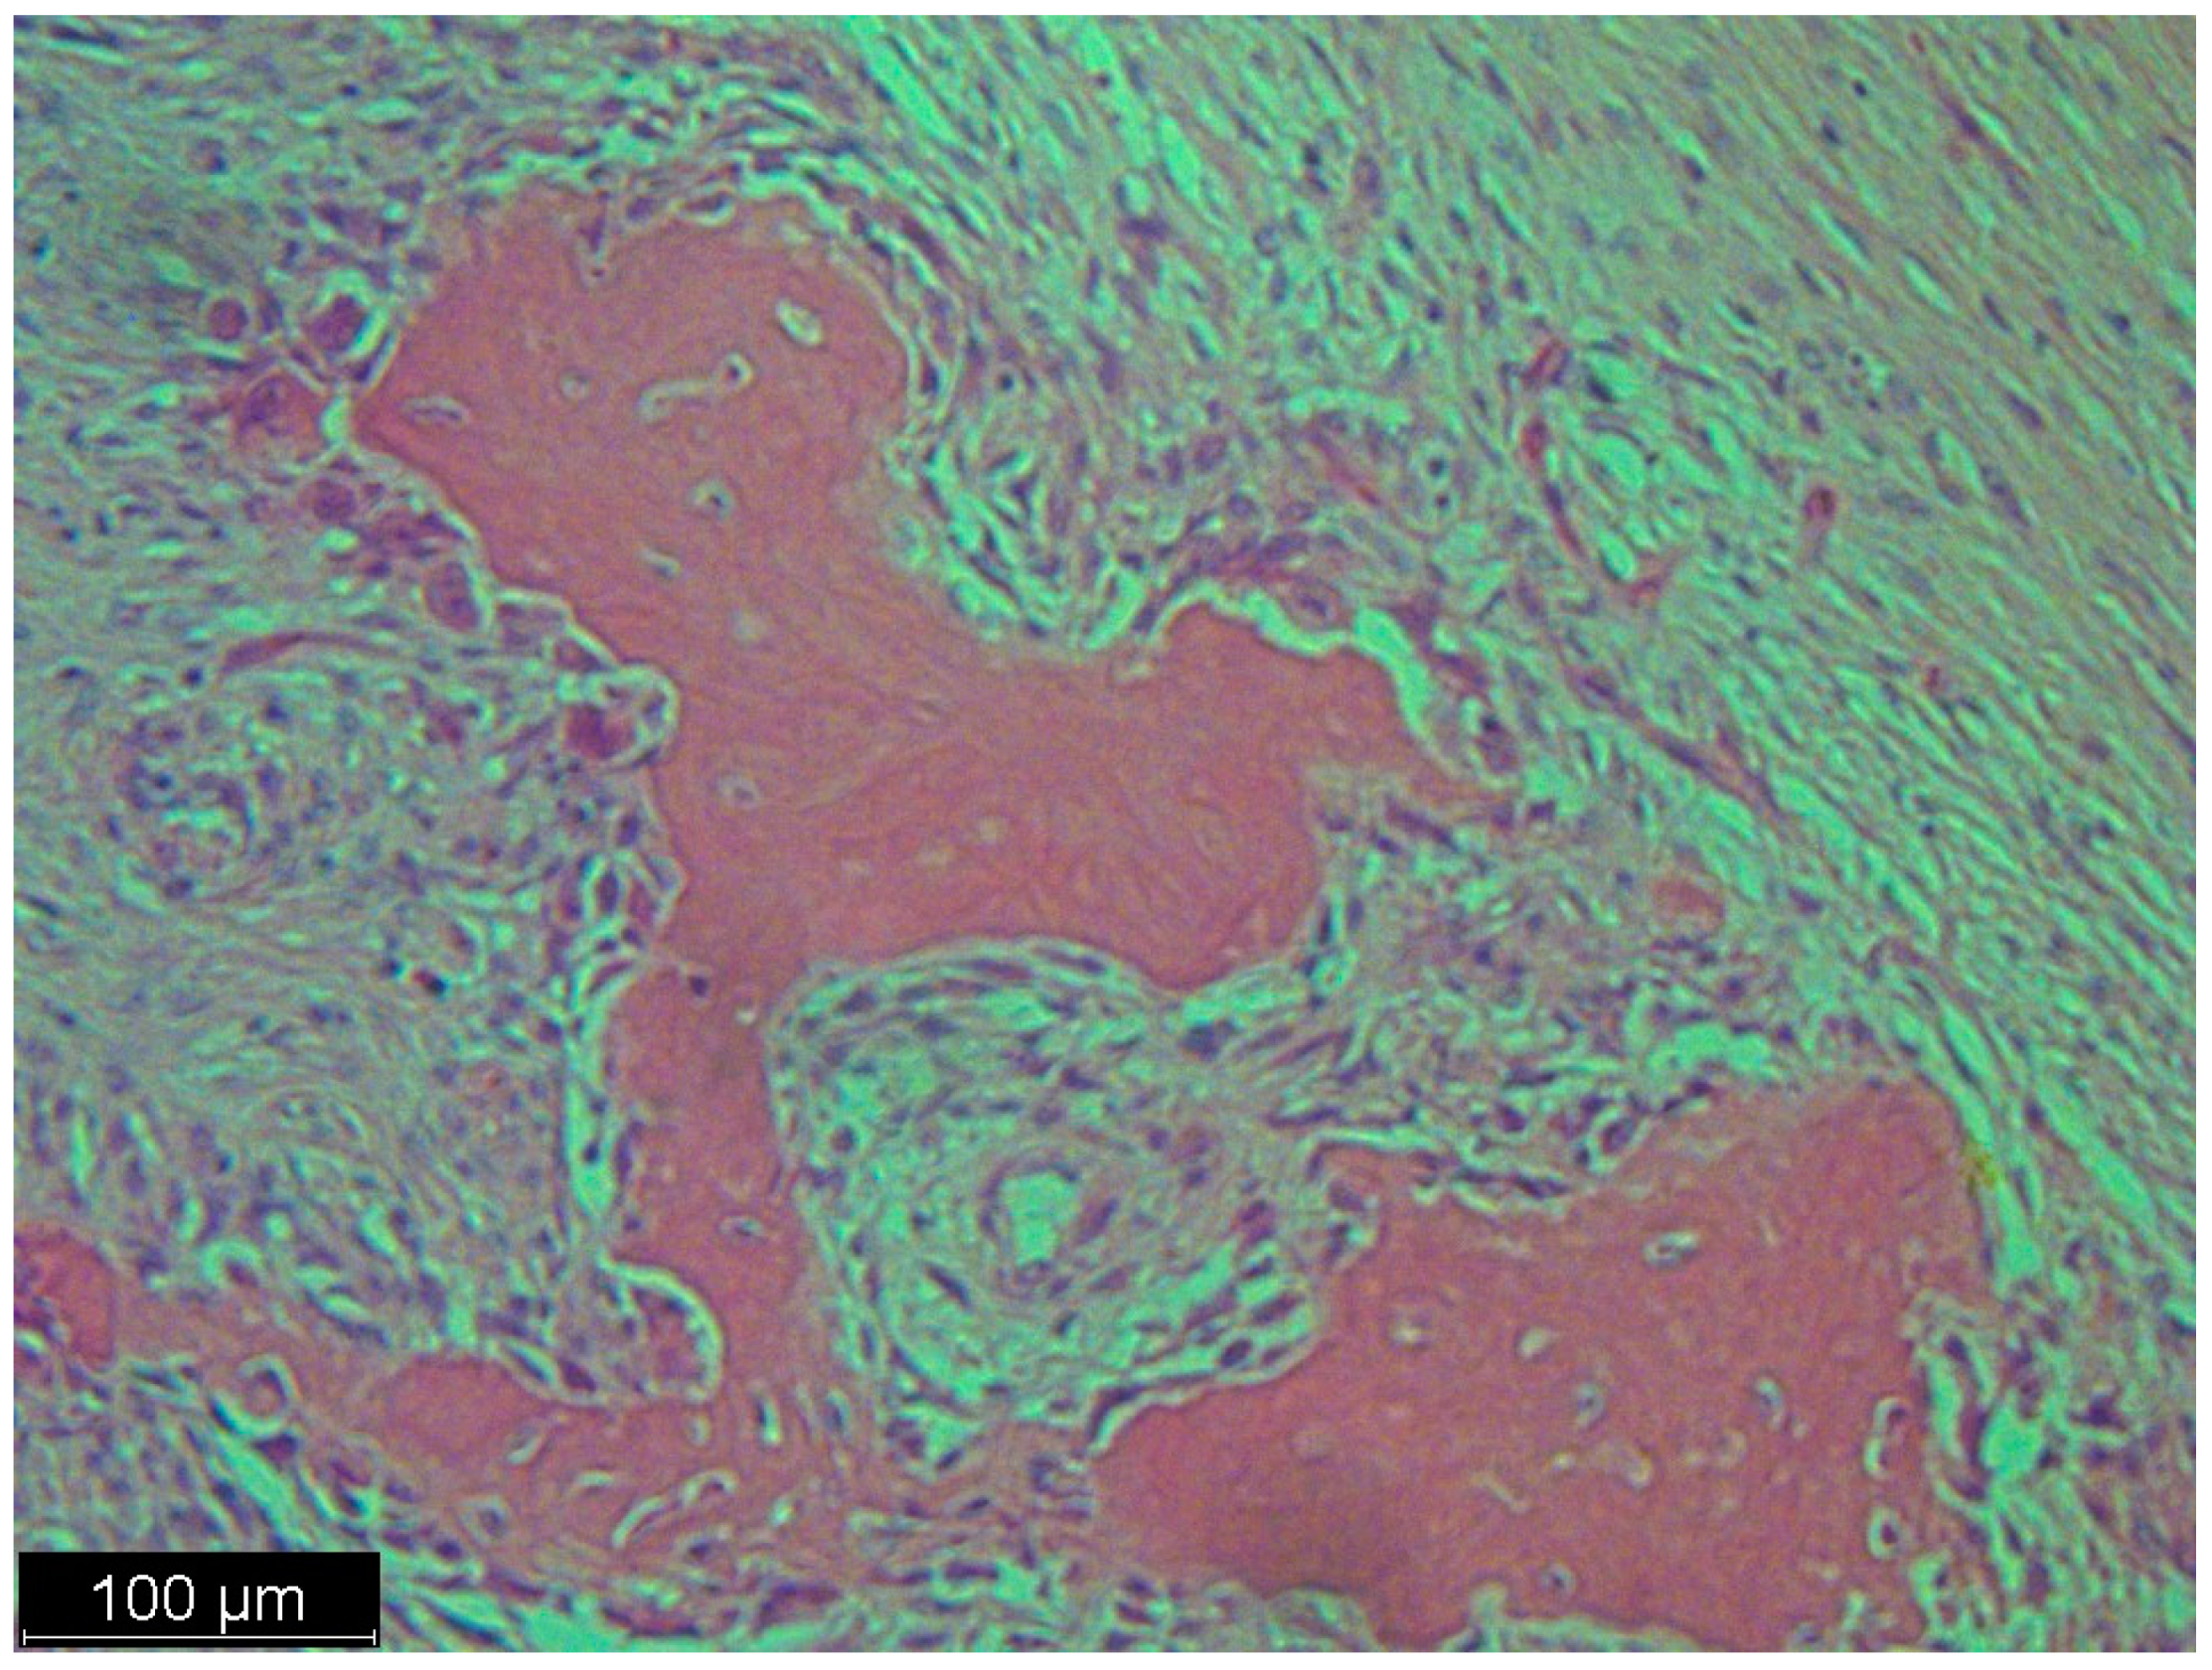

Figure 5.

This picture looked like osteosarcoma, but it was not. It was a dedifferentiated liposarcoma with a heterologous component. In this case, the tumor produced osteoids with calcified trabeculae. The photo shows an osteoblastic rimming.